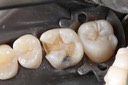

Ted Kanamori #18-19 prep